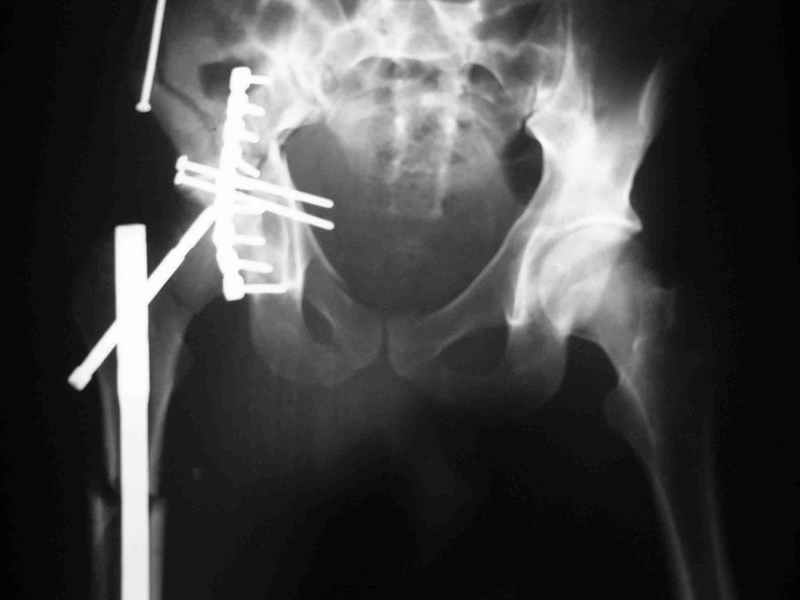

Уважаемые коллеги,Мужчина 36 лет от роду попал в ДТП 24.08.04 Рентгенограммы в приложении.

Диагноз- перелом с вовлечением таза, разрыв правого сакро-илиак сочленения vertical shear injury, перелом крыла подвздошной кости?, перелом ацетабулум Т type или Both column?, перелом шейки бедра, перелом проксимального отдела бедра.

перелом крыла правой подвздошной кости, перелом обеих колонн вертлужной впадины, двусторонний перелом лонных костей (С2.2) повреждение передних связок правого крестцово-подвздошного сочленения,

ипсилатеральный перелом шейки и диафиза бедра.

К сожалению, набора для ретроградного или антеградного реконструктивного штифтования в операционной нет, поэтому доставка заняла н-ное время. Вопрос, который возник у меня- по поводу оптимальной тактики хирургии: вся фиксация в один этап из расширенного доступа или последовательно сначала бедро и позже реконструкция впадины, комбинированный доступ к впадине отдельно к передней и задней колоннам или из расширенного илеофеморального одного доступа. Все-таки решил остановиться на одноэтапном подходе и спустя 5 дней (как раз и наборы привезли) из расширенного илеофеморального доступа сначала фиксировал реконструктивным штифтом Smith&Nephews бедро и

шейку (благо перелом шейки 2 типа -относительно стабильный) затем фрагмент крыла подвздошной кости Lag screw, далее пластина на заднюю колонну и винты в переднюю колонну.(с размерами и направлением винтов ошибка вышла:-((, но интраоперационно у меня была полная уверенность , что винты *ушли* в лонную кость).